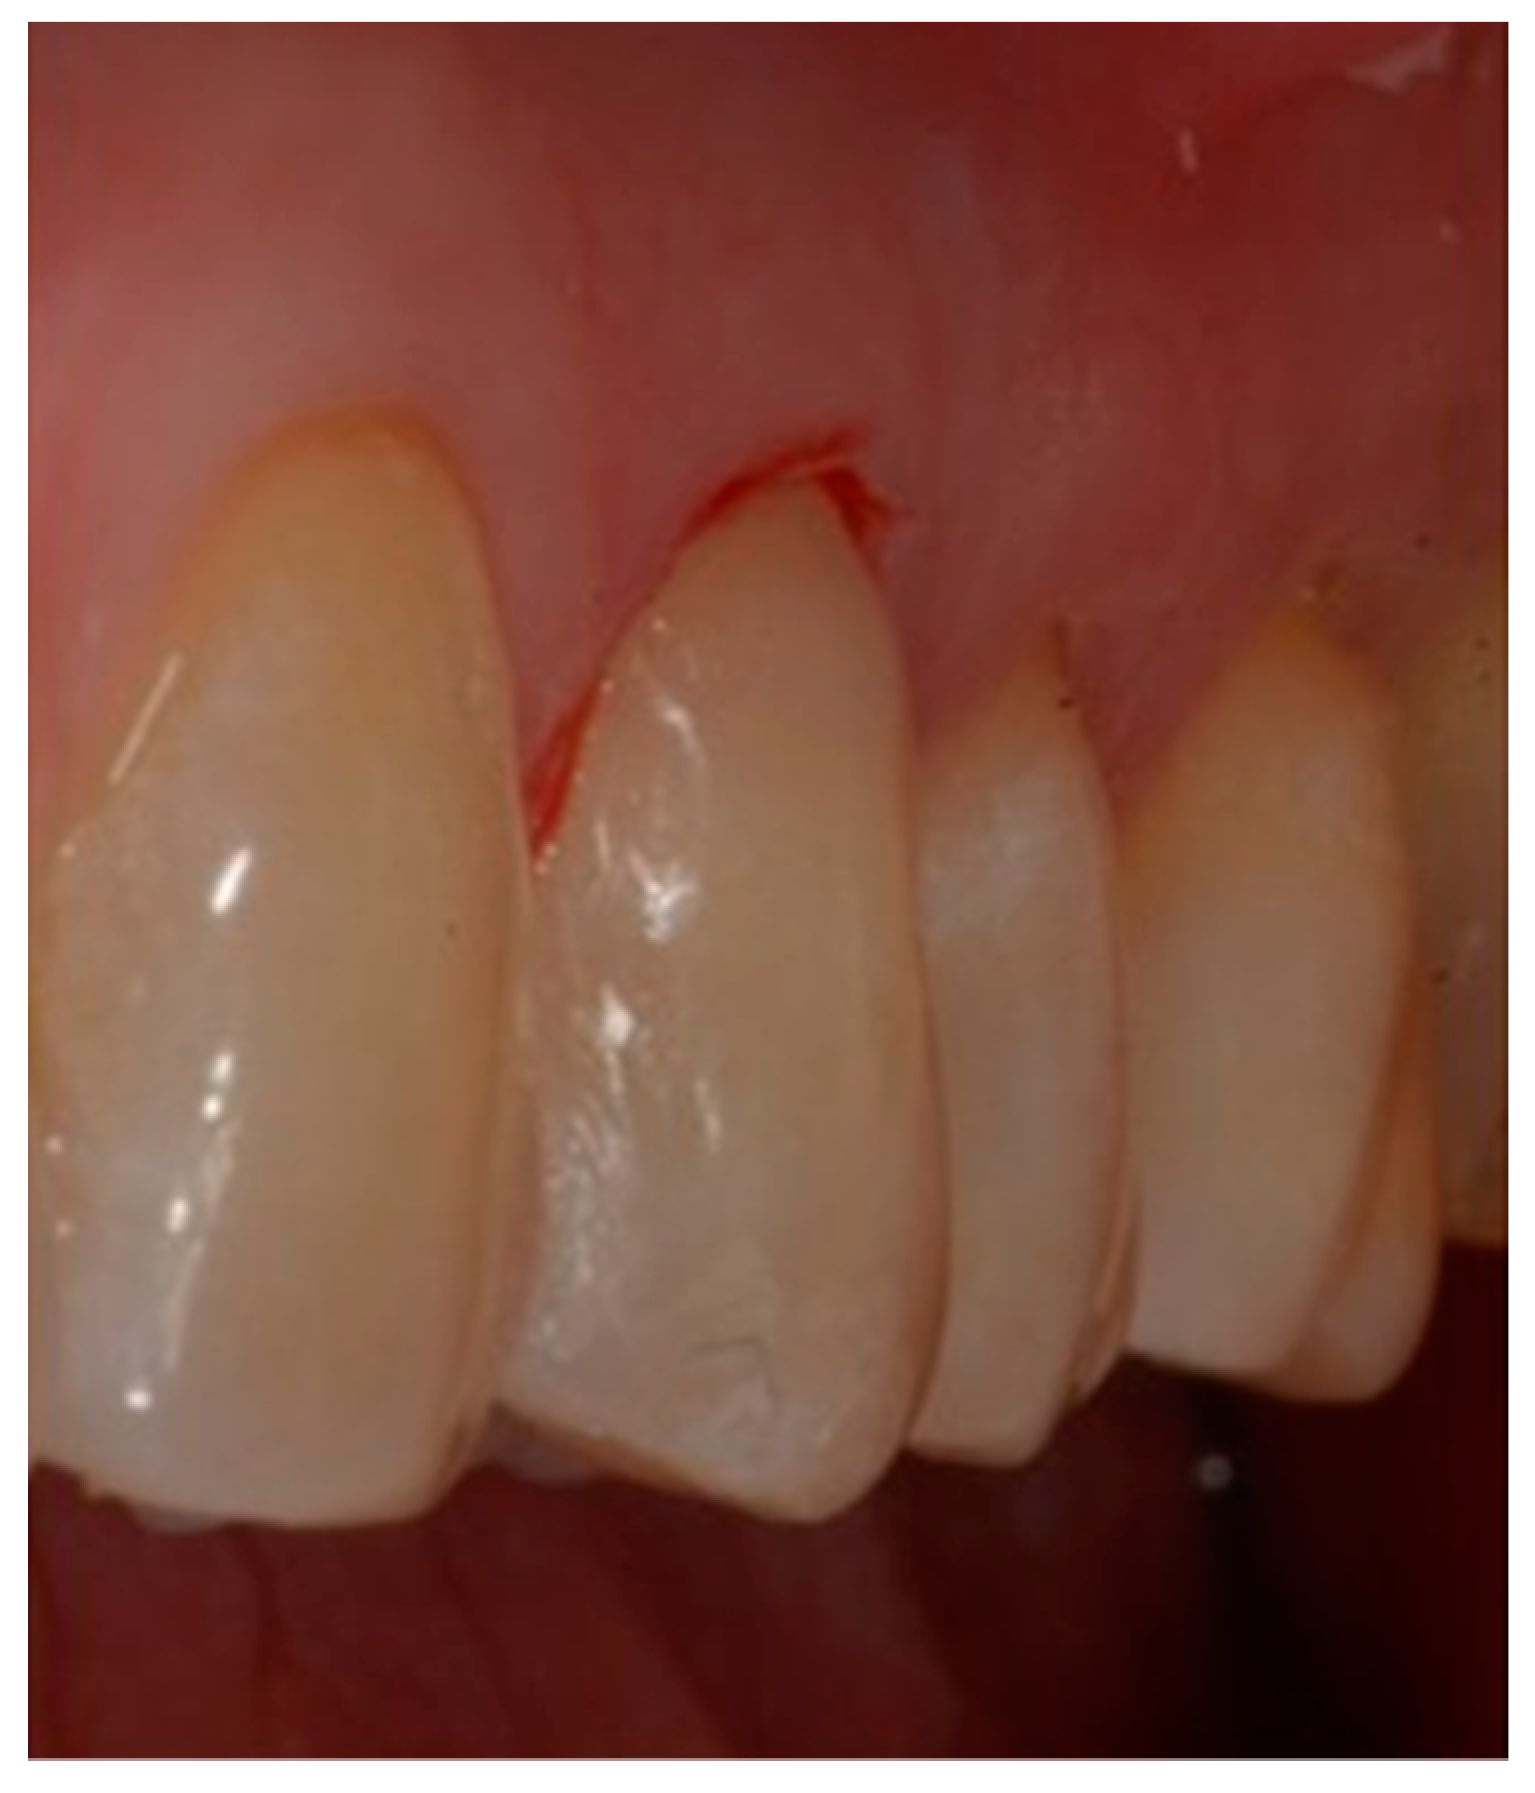

- Isolation of the field with a retraction cord 000 in the gingival sulcus (Ultrapak; Ultradent, 505 West Ultradent Drive South Jordan, UT, USA) (Figure 3).

- First refinement of the restoration and removal of the retraction cord (Figure 7).

- Finishing the restoration with a coarse- (80 μm) and a fine- (50 μm) grain flame bur placed on the most apical point of the restoration, without touching the dental tissue with the tip, in order to create an angle of approximately 45° and maintain a convex profile (Figure 8).

- Polishing the restoration with fine-grained 50 μm diamond burs, composite polishers and a brush with bristles impregnated with silicon carbide to give the restoration a perfect shine.